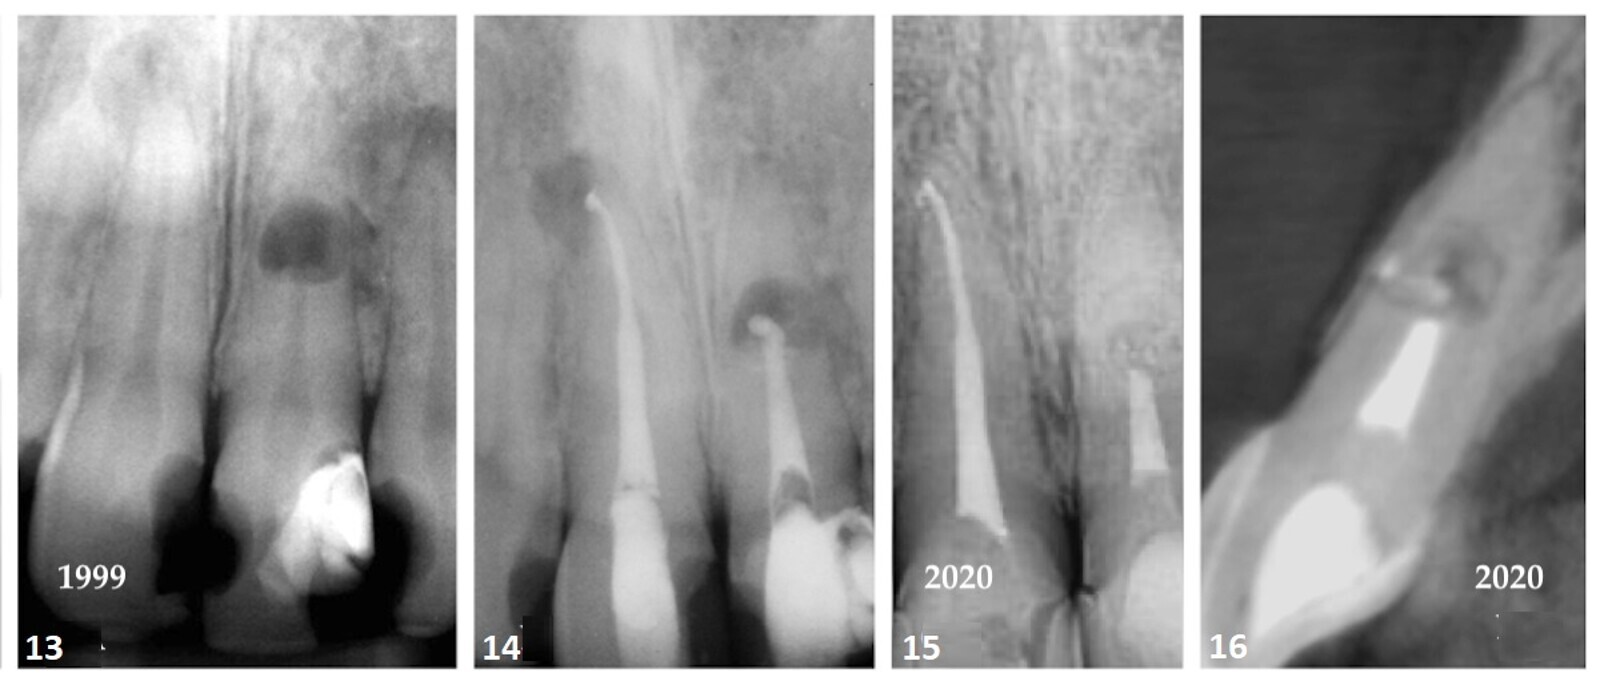

En mars 1999, une patiente de 47 ans s'est présentée au cabinet avec un gonflement du visage et la dent n° 11 était sensible à la percussion. Une radiographie périapicale du sextant antérieur maxillaire a montré de grandes restaurations de classe III et IV. La dent #11 présentait une raréfaction périapicale. La dent #21 a montré une résorption interne au niveau de la racine médiane (Fig. 13). Le patient a rapporté que la dent #21 avait été traumatisée quelque 35 ans auparavant. En l'absence d'imagerie CBCT, il a été supposé que la résorption avait perforé la face faciale de la racine et perturbé l'os cortical sus-jacent.

Les tests de sensibilité pulpaire des dents antérieures ont déterminé que la dent n° 11 était dépulpée. La dent a été traitée par endodontie et obturée à l'aide d'une technique de condensation verticale chaude. La dent n° 21 a été instrumentée au niveau incisif du défaut de résorption et le canal a été scellé avec un agrégat de trioxyde minéral blanc (Fig. 14). 13 Si la dent devait être traitée aujourd'hui, le choix du matériau d'obturation serait le mastic EndoSequence BC (Brasseler). Actuellement, il existe une tendance à l'utilisation d'une approche injectable de régénération de la fibrine riche en plaquettes pour résoudre les défauts de résorption interne qui présente un grand potentiel de guérison à long terme. 14Le suivi après 21 ans a montré que la radiotransparence périradiculaire associée à la dent n° 11 avait disparu et que le défaut de résorption avait été réduit en taille (Figs. 15 & 16).

Cas 3—fig. 13 : La radiographie intra-orale périapicale a révélé une radioclarté périradiculaire à l'apex radiculaire de la dent #11. Une grande zone de résorption interne était évidente au milieu de la racine de la dent #21. La résorption avait perforé la face latérale de la racine, provoquant une rupture de l'os interproximal. Fig. 14 : Une radiographie post-opératoire montre le traitement endodontique de la dent #11. La dent n° 21 a été scellée avec un agrégat de trioxyde minéral blanc jusqu'au niveau incisif du défaut de résorption, car elle a démontré une décoloration minimale des racines. Fig. 15 : La radiotransparence périradiculaire associée à la dent n° 11 a disparu. Le défaut de résorption a été réduit et des dépôts radiotransparents étaient évidents dans la crypte de résorption. Fig. 16 : La coupe sagittale du volume CBCT a montré une plaque corticale intacte.